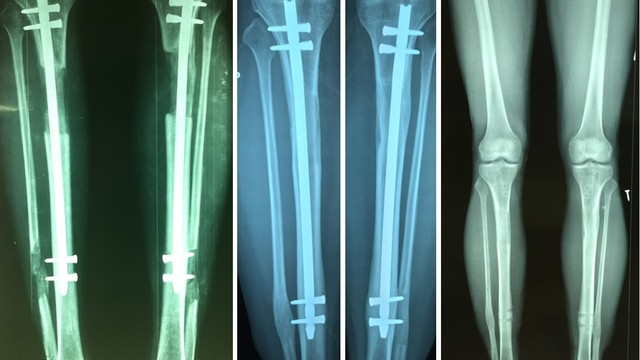

Phẫu thuật kéo dài chân là phương pháp kỹ thuật khó, đòi hỏi tay nghề chuyên môn cao của người thực hiện để đảm bảo quá trình phẫu thuật diễn ra một cách an toàn và đạt hiệu quả cao nhất.

Phẫu thuật kéo dài chân đang là một trong những phẫu thuật thẩm mỹ có được sự quan tâm của đa số các bạn trẻ. Đây là một phương pháp phẫu thuật nhằm cải thiện chiều cao một cách đáng kể. Vậy phẫu thuật kéo dài chân là gì? Chi phí phẫu thuật kéo dài chân bao nhiêu? Hãy cùng Nhà Thuốc đi tìm câu trả lời trong bài viết dưới đây nhé!